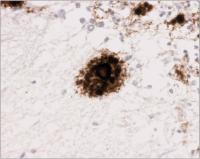

Spongiforme Enzaphalopathie - GSS - Prionprotein

Abbildung 4: GSS - multizentrische Plaques in der Kleinhirnrinde (3F4)

Keywords: AblagerungGerstmann-Sträussler-Scheinker-KrankheitGSSHistologisches PräparatKleinhirnrindeNeurologiePlaquePrionprotein